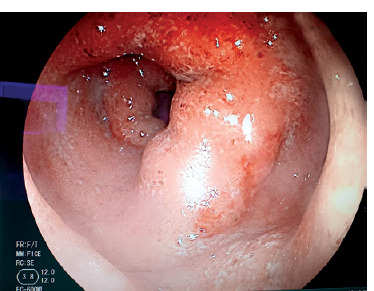

New challenges in the management of inflammatory bowel disease: a case study.